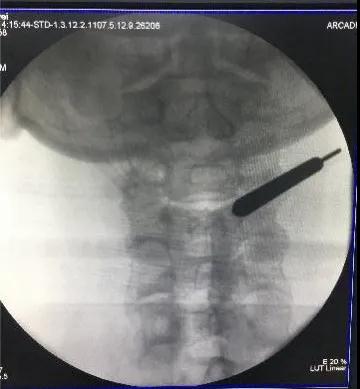

颈后路术后颈椎CT。

后入路术后见颈部椎管后方减压范围满意,骨性结构破坏小。